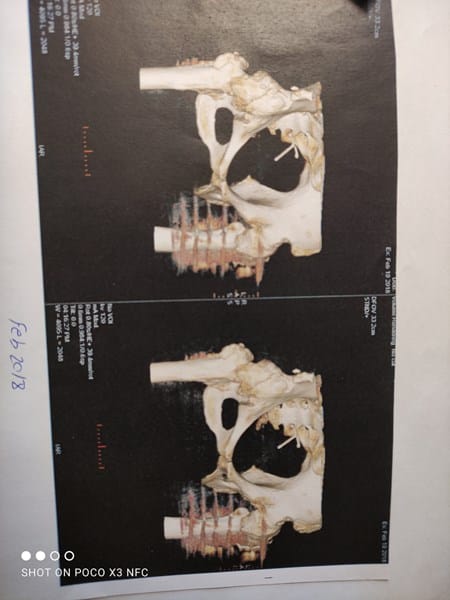

¿Qué le ocurre a esta persona en la cadera?

Soy profesora de Biología en el instituto y me han pasado una serie de TACs y radiografías de una persona a la que le pusieron posteriormente una prótesis de cadera. Este que adjunto es el TAC de antes de la operación. Me gustaría saber si se puede saber qué le pasaba a esta persona y qué es lo que sale en la imagen (las rayas de la cadera izquierda que aparecen como borrosas).